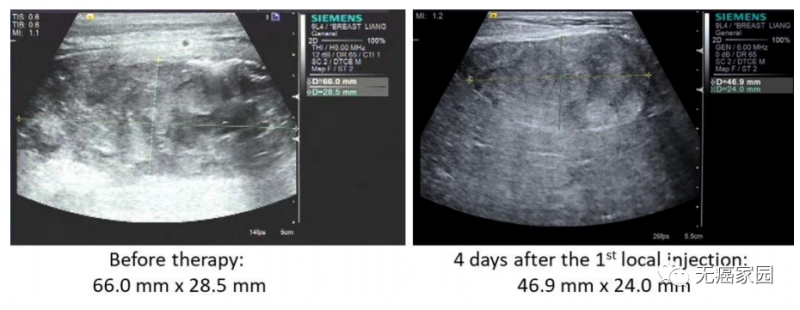

本研究中,采用局部输注 NKG2Dp CAR-NK的方式治疗了3 例转移性结直肠癌患者。前两例患者腹腔输注低剂量 CAR-NK 细胞后,可观察看腹水生成量减慢以及腹水样本中肿瘤细胞的数量急剧减少。第三例肝转移瘤患者采用超声引导下瘤内经皮注射和腹腔内灌注方式输注 CAR-NK细胞后,多普勒超声可见肝部肿瘤快速缩小,正电子发射断层扫描(PET-CT)提示经治疗的肝病灶为完全代谢反应。3 例患者在治疗过程中均无出现3级或以上的不良事件。

第3例患者多普勒超声成像显示局部注射 CAR-NK 细胞降低肝转移病灶肿瘤负荷